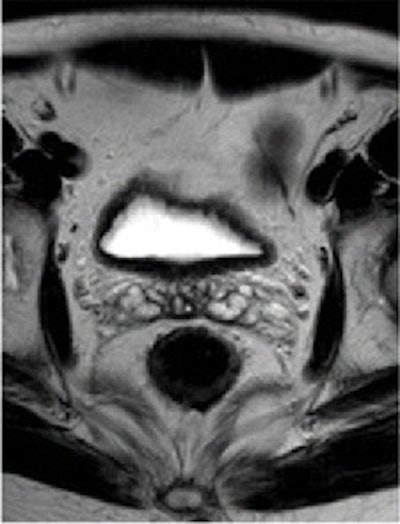

Pre- and post-treatment MRI was performed with a 1.5-tesla system (Intera R10, Philips Healthcare) using an eight-element pelvic phased-array surface coil. The subjects were imaged in the prone position after the placement of a thin rectal catheter in the rectum.

After initial localization imaging, researchers acquired MR images of the pelvis and rectum, with T2-weighted images obtained in the transverse, coronal, and sagittal planes during the scanning time of approximately 30 minutes.

Two radiologists, who were blinded to clinical information about each patient, independently evaluated the images obtained before and after chemotherapy and radiation treatment.

The MR images calculated the mean tumor volume was 58 cm3 ± 75 before chemotherapy/radiation treatment and 20 cm3 ± 31 after therapy. The mean tumor volume reduction ratio in all patients was 68% ± 23.